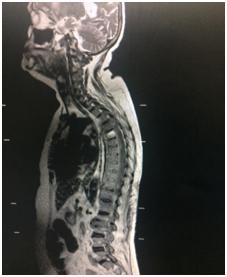

MRI showed evidence of spondylodiscitis with paraspinal and epidural inflammation at L2-L3 levels and altered signal changes at D5, D6,D7,D9,D10 & D11 - suggestive of spondylitis (Figure 1).

Figure 1 MRI on 04/06/2016.